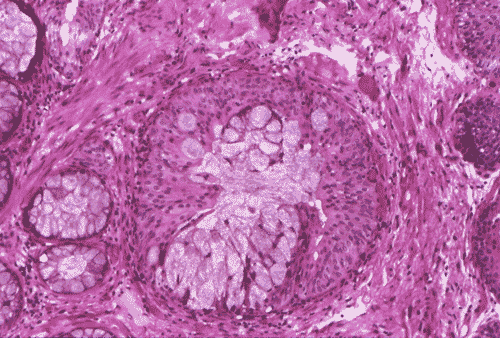

The biopsy material showed polypoid fragments with cystically dilated glands lined by columnar to cuboidal cells (Panel A, B, and C). Some of the glands were lined by transitional epithelium (Panel D), some were lined by a mixed transitional epithelium and mucin producing columnar epithelium (Panel E), and some were lined entirely by mucin producing columnar epitheliuim (Panel F) that closely resembled colonic epithelium. A mild to moderate degree of chronic inflammatory cell infiltration was also present. A mixed population of mucin producing columnar epithelium with transitional epithelium was also noted in many of the non-glandular surface epithelium (Panel G). No dysplasia was found.

DIAGNOSIS: Polypoid cystitis cystica et glandularis, intestinal type.

The typical type of cystitis glandularis contains simple cuboidal to columnar cells. Small amount of mucin may be present but the amount is usually not impressive. The intestinal type contains epithelium with intestinal metaplasia. These type has numerous goblet cells and tubular epithelium that morphologically resemble colonic epithelium and contains colonic type mucin 5, 6 . Paneth cells metaplasia can also be seen in this type. Cystitis glandularis is associated with increased risk of adenocarcinoma 1, 3, 4, 5, 7, 8. Patients with extensive and diffuse intestinal metaplasia are particularly prone to develop adenocarcinoma 8.

The histopathologic diagnosis of cystitis glandularis and cystica rarely poses a real diagnostic problem. The most important distinction is between this benign lesion and adenocarcinoma.  Cystitis glandularis and cystica usually lacks the nuclear atypia and stromal reaction seen in invasive adenocarcinoma. Furthermore, glands in cystitis glandularis are smooth in contour while those of adenocarcinoma are more irregular and give an infiltrative architectural pattern. Deep location, irregular contour, desmoplastic reaction, and nuclear atypia are features that suggest adenocarcinoma 9. Substantial mucin extravasation into the stroma can be seen in some cases of the intestinal type of cystitis glandularis, the distinction between cystitis glandularis and adenocarcinoma may be difficult in these cases 10, 11, 12.